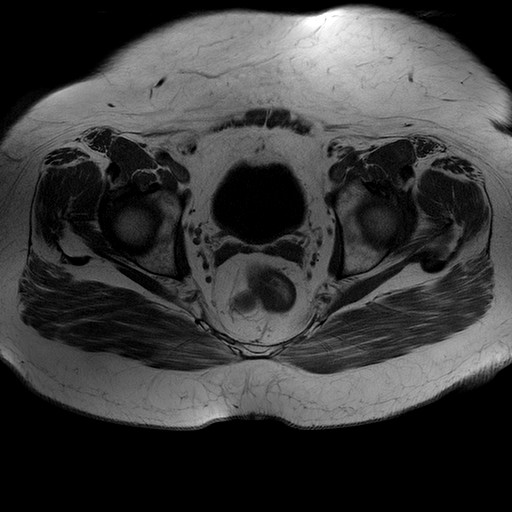

Esami: RMN BACINO

T1W_TSE

Evidenti e simmetriche alterazioni osteofitosiche in regione coxo femorale con riduzione delle rime articolari. Degenerazione completa del cercine glenoideo. Non attuali segni di versamento articolare. Non segni di edema osseo che escludono attuale algodistrofia od osteonecrosi. Lieve e simmetrica riduzione del trofismo della muscolatura glutea.